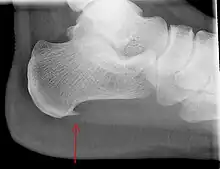

An incidental finding associated with this condition is a heel spur, a small bony calcification on the calcaneus (heel bone), which can be found in up to 50% of those with plantar fasciitis.[6] In such cases, it is the underlying plantar fasciitis that produces the heel pain, and not the spur itself.[13] The condition is responsible for the creation of the spur though the clinical significance of heel spurs in plantar fasciitis remains unclear.[12]

Imaging

Medical imaging is not routinely needed. It is expensive and does not typically change how plantar fasciitis is managed.[15] When the diagnosis is not clinically apparent, lateral view X-rays of the ankle are the recommended imaging modality to assess for other causes of heel pain, such as stress fractures or bone spur development.[7]